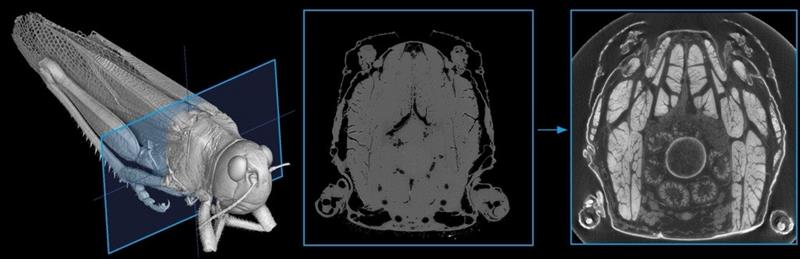

W13: X-ray Computed Microtomography

Can we visualise the brain and nerves using X-rays? X-ray computed microtomography (microCT) is a non-destructive imaging technique that can serve as a powerful tool in biological research. In this workshop, we will explore the possibilities and limitations of microCT for neural imaging by examining biological samples ex vivo.

Scope of Activity:

- MicroCT Scanning: First, we will prepare samples for microCT scanning. Participants will learn how to mount specimens so they can rotate 360° during acquisition and how to select appropriate scanning parameters. We will then launch a scan and evaluate the results.

- Phase Contrast or Staining? Next, we will discuss strategies for increasing soft-tissue contrast, including phase-contrast imaging and contrast-agent staining. A second scan will be performed, and the two datasets will be compared to determine which approach provides better results for analysis.

- Creation of a 3D Model: Finally, we will introduce basic image analysis concepts and demonstrate approaches for creating and exploring 3D reconstructions.

No previous experience is required. In this half-day workshop, we will cover the fundamentals of X-ray microCT imaging and discuss its possibilities and challenges.

Duration: ½ day